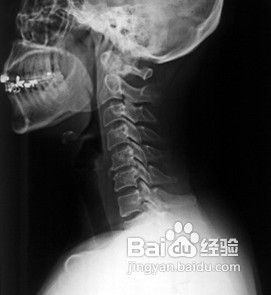

随着生活压力的增大,患有颈椎病的人也越来越多,了解颈椎病的预防方法对有效避免颈椎病的发生有着关键作用。那么我们可以怎样预防颈椎病的发生?

1、注重姿势,良好的姿势是预防颈椎病的有效办法,常言说“坐如钟”也可以应用到颈椎病的治疗上来,身体健康者及患者不宜长期低头工作,工作期间应适当休息,并配合做颈部运动;读书、看报时坐姿要正,睡眠时枕头不宜过高。

5、枕头合适,合适的枕头对预防和治疗颈椎病有重要意义。一般仰卧者枕高一拳,侧卧者枕高一拳半,约10cm左右。枕芯以木棉、荞麦皮为好,装填量要适当,以保持一定的硬度和弹性。弹性过大的枕头容易造成颈部肌肉的疲劳和损伤。习惯仰卧者最好在颈下垫一小枕头,以保持颈椎的生理弯曲。习惯侧卧者应将枕头充塞到面部与肩部的空隙中,以减轻颈部的负担。